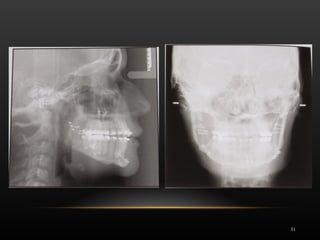

DIAGNÓSTICO

 Desviación mandibular a la derecha 5mm

 Clase III esquelética por prognatismo mandibular

 No problema vertical 

 Exposición incisivo en sonrisa 80%

 Sonrisa asimétrica con menor movilidad parte derecha labio inferior

 Falta proyección del mentón

 Labio inferior protruido sin ángulo mentolabial

Mujer, 20 años